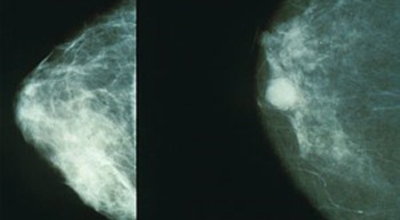

2. 유방암 초기증상 - 유방의 혹

보통 응어리가 잡히는 분들의 40%는 물혹으로 가벼운 질병으로 바로 치유가 되는 경우가 많은데요 20~30%의 확률로 유방암 초기증상일 가능성이 있다고 하죠. 따라서 매일같이 자신의 가슴을 마사지 해주시다 어느 날 응어리가 잡히게 된다면 유방암 검사 초기에 받아 보시기를 권해 드립니다.